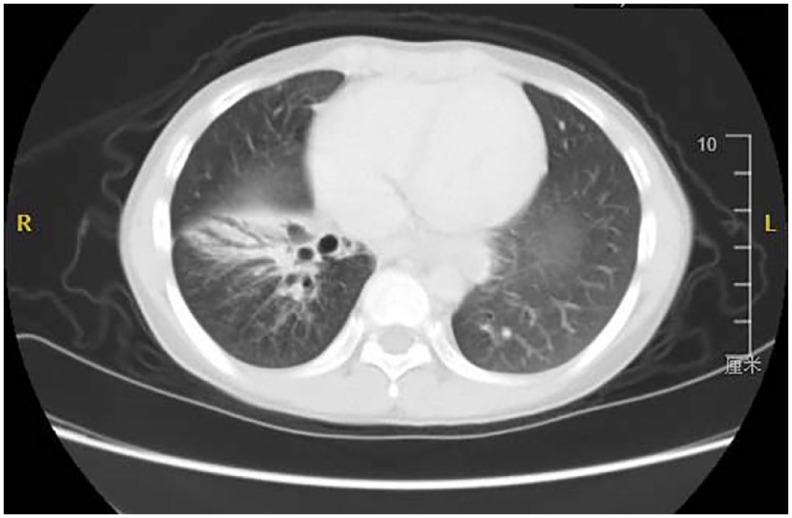

Background: Pediatric bronchiectasis is a common respiratory disease in children. The use of video-assisted thoracoscopic surgery (VATS) for its treatment remains controversial.

Methods: A retrospective analysis was conducted on the clinical data of 46 pediatric patients who underwent surgery with bronchiectasis at the Children's Hospital of Chongqing Medical University from May 2015 to May 2023. The patients were divided into two groups: the VATS group (25 cases) and the thoracotomy group (21 cases). Comparative analysis was performed on various parameters including basic clinical data, surgical methods, operation time, intraoperative blood loss, transfusion status, postoperative pain, postoperative mechanical ventilation time, chest tube drainage time, length of hospital stay, incidence of complications, and follow-up information.

Results: There were no statistically significant differences between the two groups of patients in terms of age, weight, gender, etiology, duration of symptoms, site of onset, and comorbidities (p > 0.05). The operation time in the VATS group was longer than that in the thoracotomy group (p < 0.001). However, the VATS group had better outcomes in terms of intraoperative blood loss, transfusion status, postoperative pain, postoperative mechanical ventilation time, chest tube drainage time, and length of hospital stay (p < 0.05). The incidence of postoperative complications in the VATS group was lower than that in the thoracotomy group, although the difference was not statistically significant (p = 0.152). Follow-up data showed no statistically significant difference in the surgical treatment outcomes between the two groups (p = 0.493).

Conclusion: The incidence of complications and mortality in surgical treatment of bronchiectasis is acceptable. Compared with thoracotomy surgery, VATS has advantages such as smaller trauma, less pain, faster recovery, and fewer complications. For suitable pediatric patients with bronchiectasis, VATS is a safe and effective surgical method.